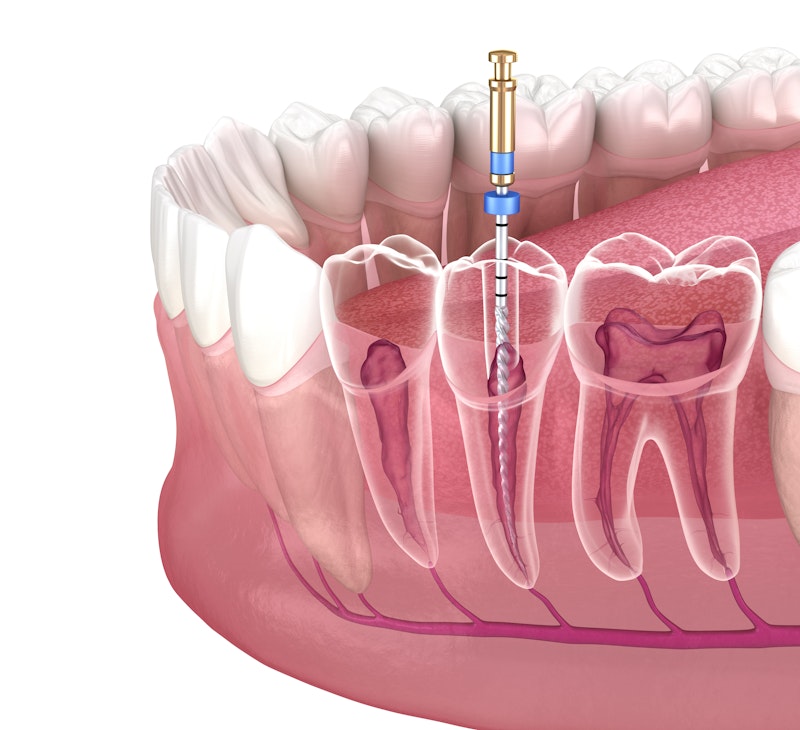

Take a Closer Look at Root Canal Treatment

Root Canal Treatment, Step by Step

Once the infection has spread to the pulp chamber, only root canal treatment can prevent the extraction of a tooth.